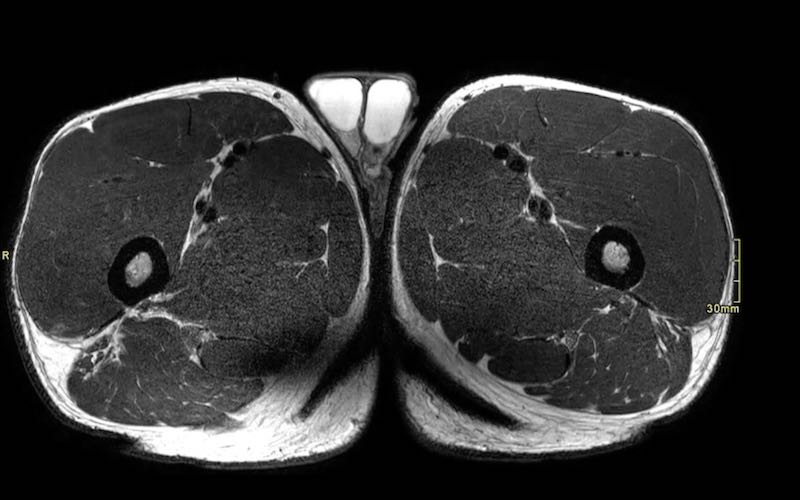

MRI protocol based on pulse sequences: coronal fatsat, axial PD fatsat and axial T2.

- Chuỗi xung T2 xóa mỡ mặt phẳng coronal (fatsat, STIR hoặc dixon) cho phép đánh giá tổng quan nhanh chóng về tổn thương và giúp đo lường dễ dàng các khoảng cách liên quan (ví dụ: chiều dài vùng phù nề hoặc mức độ co rút gân).

- Chuỗi xung PD xóa mỡ mặt phẳng axial (fatsat hoặc dixon) tập trung vào vùng tổn thương và cho phép đánh giá đầy đủ tình trạng phù nề hoặc tụ máu, bao gồm cả trong cơ lẫn giữa các cơ.

- Chuỗi xung T2 mặt phẳng axial từ điểm nguyên ủy đến điểm bám tận cho phép hiển thị chi tiết tổn thương gân. Các hình ảnh độ phân giải cao này rất hữu ích để đánh giá giải phẫu và mức độ tổn thương trên từng bó sợi riêng lẻ. Thông thường cần hai khối chụp (stack).

Toàn bộ phức hợp cơ hamstring của cả hai chân cần được khảo sát trên tất cả các chuỗi xung để so sánh bên tổn thương với bên hamstring lành.

Đặc biệt, các tổn thương một phần có thể rất khó phát hiện.

Chúng tôi chỉ sử dụng mặt phẳng coronal và axial để đánh giá giải phẫu, vì việc đánh giá giải phẫu trên mặt phẳng sagittal thường khó khăn hơn.